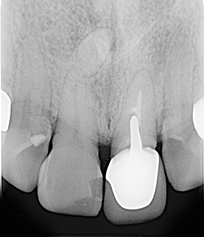

假牙拆除前的X光片,可看出假牙已不密合